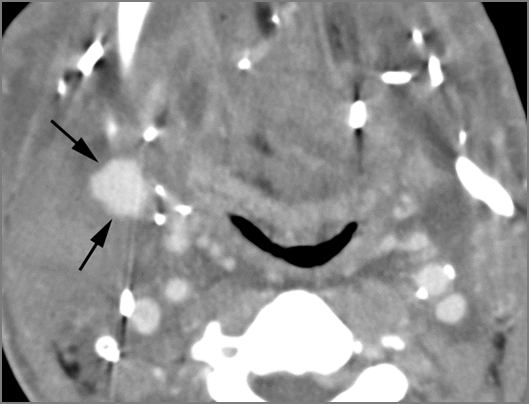

Cervical Lymph Nodes

If there is suppurative cervical adenopathy the purulent material outside the lymph node(s) capsule(s).